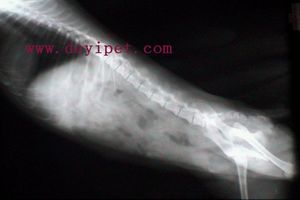

1.X線檢查心臟擴大,心臟搏動有力。肺動脈弓突出,心臟呈興奮性高動力型球形甲亢心。如有長期心房纖顫或心力衰竭者,可見心影增大。有嚴重心力衰竭時,心影向兩側擴大。